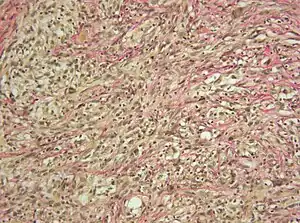

Micrograph showing a gliosarcoma. Elastic van Gieson's stain.

a) Gliomatous component GFAP positive b) biphasic tissue pattern with glial and mesenchymal differentiation c)sarcomatous component vimentine positive